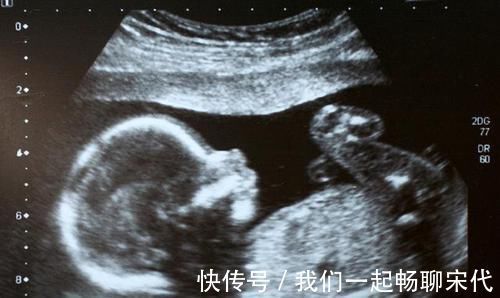

文章插图

在宝宝在妈妈肚子里发育的过程中,大脑的发育主要是分为三个阶段,第一个阶段是细胞数目大量增加的阶段。第二个阶段是脑细胞的数目增加与脑细胞体积增大阶段,第三个阶段则是脑细胞数目不便而体积增大的阶段。